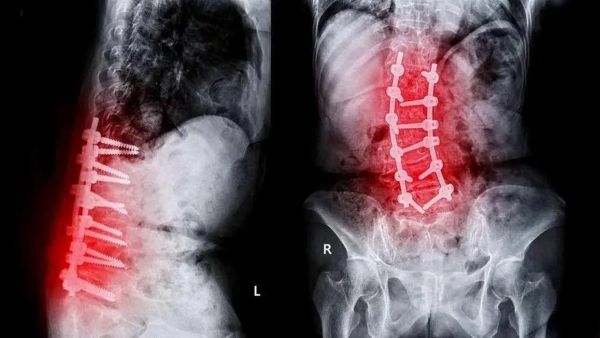

“筋骨层”:椎间盘退化、韧带钙化,如同年久失修的轴承,需针对性锻炼;